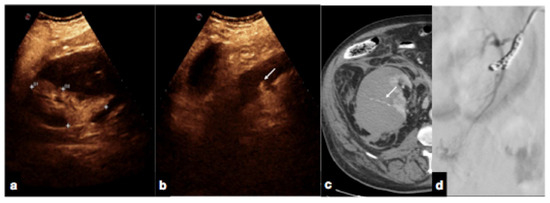

Active bleeding can be observed as micro-bubble extravasation outside blood vessels within the peritoneal or retroperitoneal space (Figure 17) [1,30].

Figure 17.

Follow-up CEUS of a 52−year-old blunt trauma patient with high-grade right kidney injury and extensive ischemia complication. Venous (a) phase CEUS examination shows multiple kidney lacerations with extensive ischemia complication and a small amount of perfused renal (caliper). At the same venous phase (b), CEUS active venous hemorrhage is well appreciated (arrow) confirmed at contrast-enhanced venous phase CT scan (c, arrow) and subsequent angiography (d).

- Contained vascular injuries:

Contained vascular injuries include pseudoaneurysms and arteriovenous fistulas. Pseudoaneurysms are focal outpouchings of the external vessel contour due to the partial disruption of the wall, which is contained by the tissue around the vessel (Figure 18, Figure 19 and Figure 20) [1,30].

Figure 20.

CEUS (a) of a 23−year-old man referring to the emergency department for direct blunt trauma to the right flank showed the presence of a small pseudoaneurysm (white arrow) inside the contusion area of the right kidney; the diagnosis was then confirmed at the axial arterial phase contrast-enhanced CT scan (b), as well as at angiography performed for treatment purposes (c).

Arteriovenous fistulas consist of traumatic communication between the arterial and venous systems [1,30]. Fistulas are characterized as asymmetrical, early contrast opacification of a vein during the early arterial phase of the study (Figure 21).

Figure 21.

Companion case of Figure 2b. Renal arteriovenous fistula (white arrowhead) at color–Doppler US (a) and CEUS (b), confirmed (c) at contrast-enhanced CT scan (arterial phase, coronal MIP reconstruction) and subsequent angiography (d).